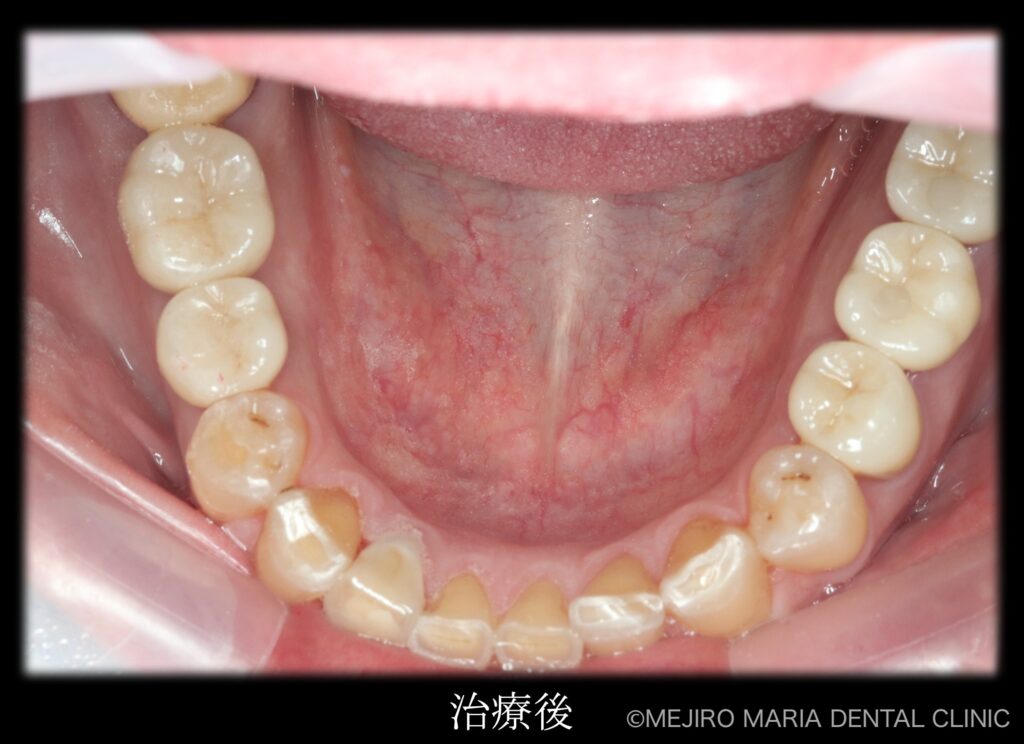

治療後の様子

各分野の専門医(精密根管治療専門医・インプラント専門医・口腔外科専門医)が最善を尽くすことで、より高度な治療をスピーディーに終えることができました。

そのため、抜歯の際はまず口腔外科医が不良肉芽を確実に除去します。その後、骨がインプラント埋入に耐えられるよう、インプラント専門医がGBR(骨造成)やソケットリフトを施して不足している骨の再生治療を行ってから、インプラントを安全に埋入しました。そのほか、既に根管治療済みの歯で保存できると判断したものは、精密根管治療専門医が保存の処置をしました。

最終段階に入る前に、仮歯の状態で咬合の安定が確認できたことから、最終補綴処置を行いました。最終補綴処置後の経過は良好で、今後はメンテナンスをしながらインプラントを含めた根尖周囲組織、補綴物(被せ物)の長期的な経過を確認していきます。